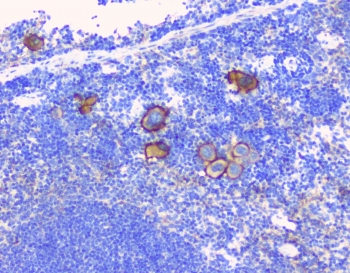

T-lymphocyte surface antigen Ly-9 is a protein that in humans is encoded by the LY9 gene. This gene is mapped to 17q21.31. LY9 has also recently been designated CD229 (cluster of differentiation 229). LY9 belongs to the SLAM family of immunomodulatory receptors and interacts with the adaptor molecule SAP.

Amino acids YKAQINQRNFEVTTEEEFTLFVYEQLQEPQVTMK were used as the immunogen for the CD229 antibody.